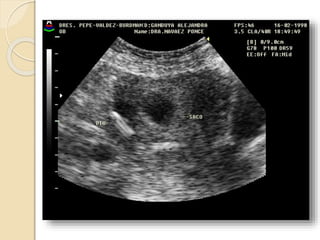

FIBROMA O LEIOMIOMA UTERINO

Patología común del útero que ocurre aproximadamente

en el 40% de las mujeres mayores de 35 años.

Los fibromas habitualmente son múltiples y más

comúnmente asintomáticos.

Se clasifican en:

• Submucosos: son los menos frecuentes pero es mas

probable que produzcan síntomas.

• Intramurales: Es el tipo mas común.

• Subserosos: Con frecuencia son pediculados y

pueden simular masas anexiales.